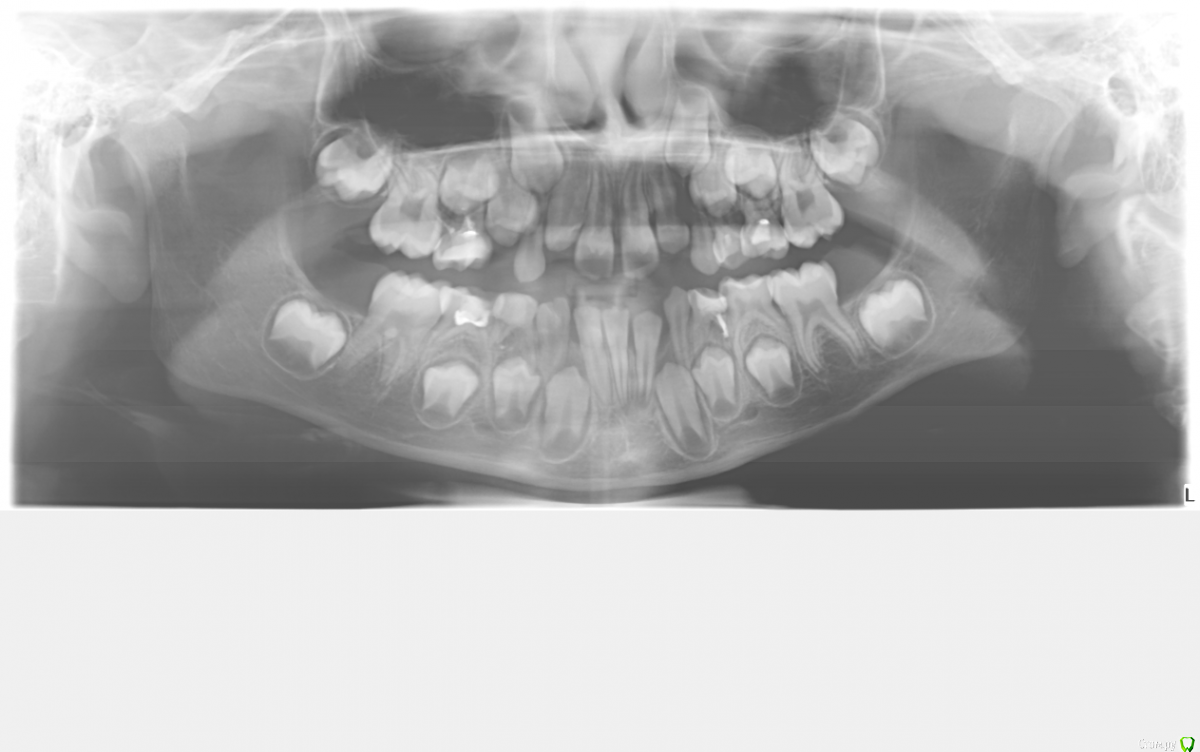

crown Опубликовано 20 марта, 2017 Поделиться Опубликовано 20 марта, 2017 Я не ортодонт, просто интересно. 8 лет. Нет зачатка 42, 83 аномальный, сросшийся, поражен кариесом. Центральная линия смещена. Интересует судьба 43. Ссылка на комментарий

Yana guapa Опубликовано 20 марта, 2017 Поделиться Опубликовано 20 марта, 2017 Интересует судьба 43.а что именно смущает с 4.3? Ссылка на комментарий

crown Опубликовано 20 марта, 2017 Автор Поделиться Опубликовано 20 марта, 2017 Так не красиво будет и не правильно, центральный резец и сразу клык Ссылка на комментарий